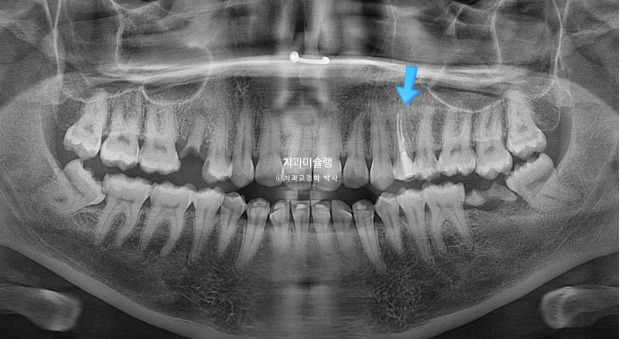

In the area of the missing mandibular molar, the site had been left untreated for a long period. As a result, the opposing tooth (indicated by the blue arrow) had supra-erupted.

For proper implant placement, this opposing tooth needs to be intruded through orthodontic treatment.

The treatment plan involves first closing the extraction spaces by retracting the protruded anterior teeth, followed by sequential intrusion of the supra-erupted molar.